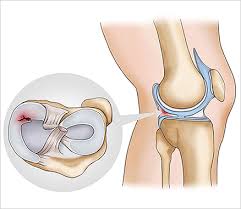

무릎 연골 손상 증상은 다양한 원인에 의해 발생할 수 있으며, 이는 일상생활과 운동에 큰 영향을 미칩니다. 무릎 연골 손상 증상은 주로 무릎 통증, 부종, 뻣뻣함 등으로 나타나며, 특히 무릎을 구부리거나 펼 때 '뚝' 소리가 나기도 합니다. 이러한 증상이 발생하면 즉각적인 대처가 필요합니다. 무릎 연골 손상 증상은 방치할 경우 퇴행성 관절염과 같은 이차적인 질환으로 이어질 수 있기 때문에 빠른 진단과 치료가 중요합니다.

무릎 연골 손상 증상은 단순한 무릎 통증으로 끝나지 않고 다양한 동반 증상과 함께 나타납니다. 일반적으로 무릎 부위의 붓기와 불편함이 동반되며, 특히 무릎의 안쪽이나 바깥쪽에서 통증이 느껴질 수 있습니다. 또한, 무릎을 움직일 때 '잠김 현상'이 발생하기도 하며, 이는 무릎 연골 손상 증상이 심한 경우 나타나게 됩니다. 이러한 증상들은 운동 후나 오랜 시간 앉아 있다가 일어날 때 더욱 심해질 수 있습니다.